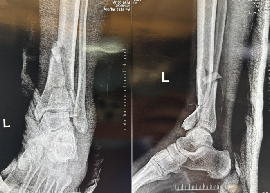

Expert care for all your foot and ankle problems. From injuries to long-term pain, Dr. Vishal Yadav provides personalized treatment to help you walk pain-free and live better.

Minimally Invasive Surgery (MIS) :

- Ankle Arthroscopy

- Endoscopic Calcaneoplasty

- Posterior Arthroscopy